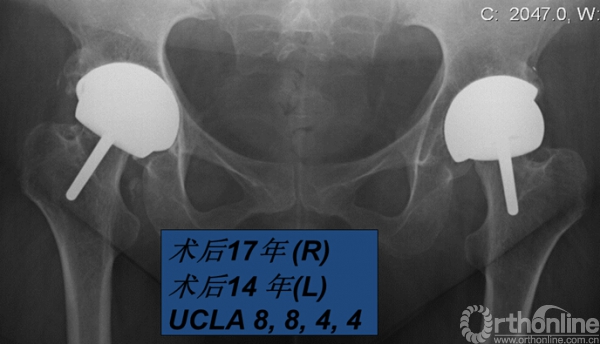

我使用CONSERVE® PLUS系统治疗101例股骨头坏死,平均年龄41岁,80%男性,平均随访11.8年(1-17.3),假体5年生存率96.7%,13年93.7%(n=23)。使用骨水泥型股骨假体的病例未出现股骨假体失败(图1)。治疗125例DDH,平均年龄47.5岁,74%女性,平均随访10.7年(2.5-17.3),股骨头尺寸44.6mm (36-54),假体5年生存率94.6%,10年84.7%,13年79.8%。而第二代和第三代Conserve®Plus表面髋关节假体的12年生存率高达92%(图2)。治疗13例类风湿关节炎,平均年龄36岁,60%男性,平均随访时间11年(7-17),随访期内假体生存率100%(图3)。

图3. 36岁女性患者,青少年类风湿性关节炎,右侧术后17年,左侧术后14年